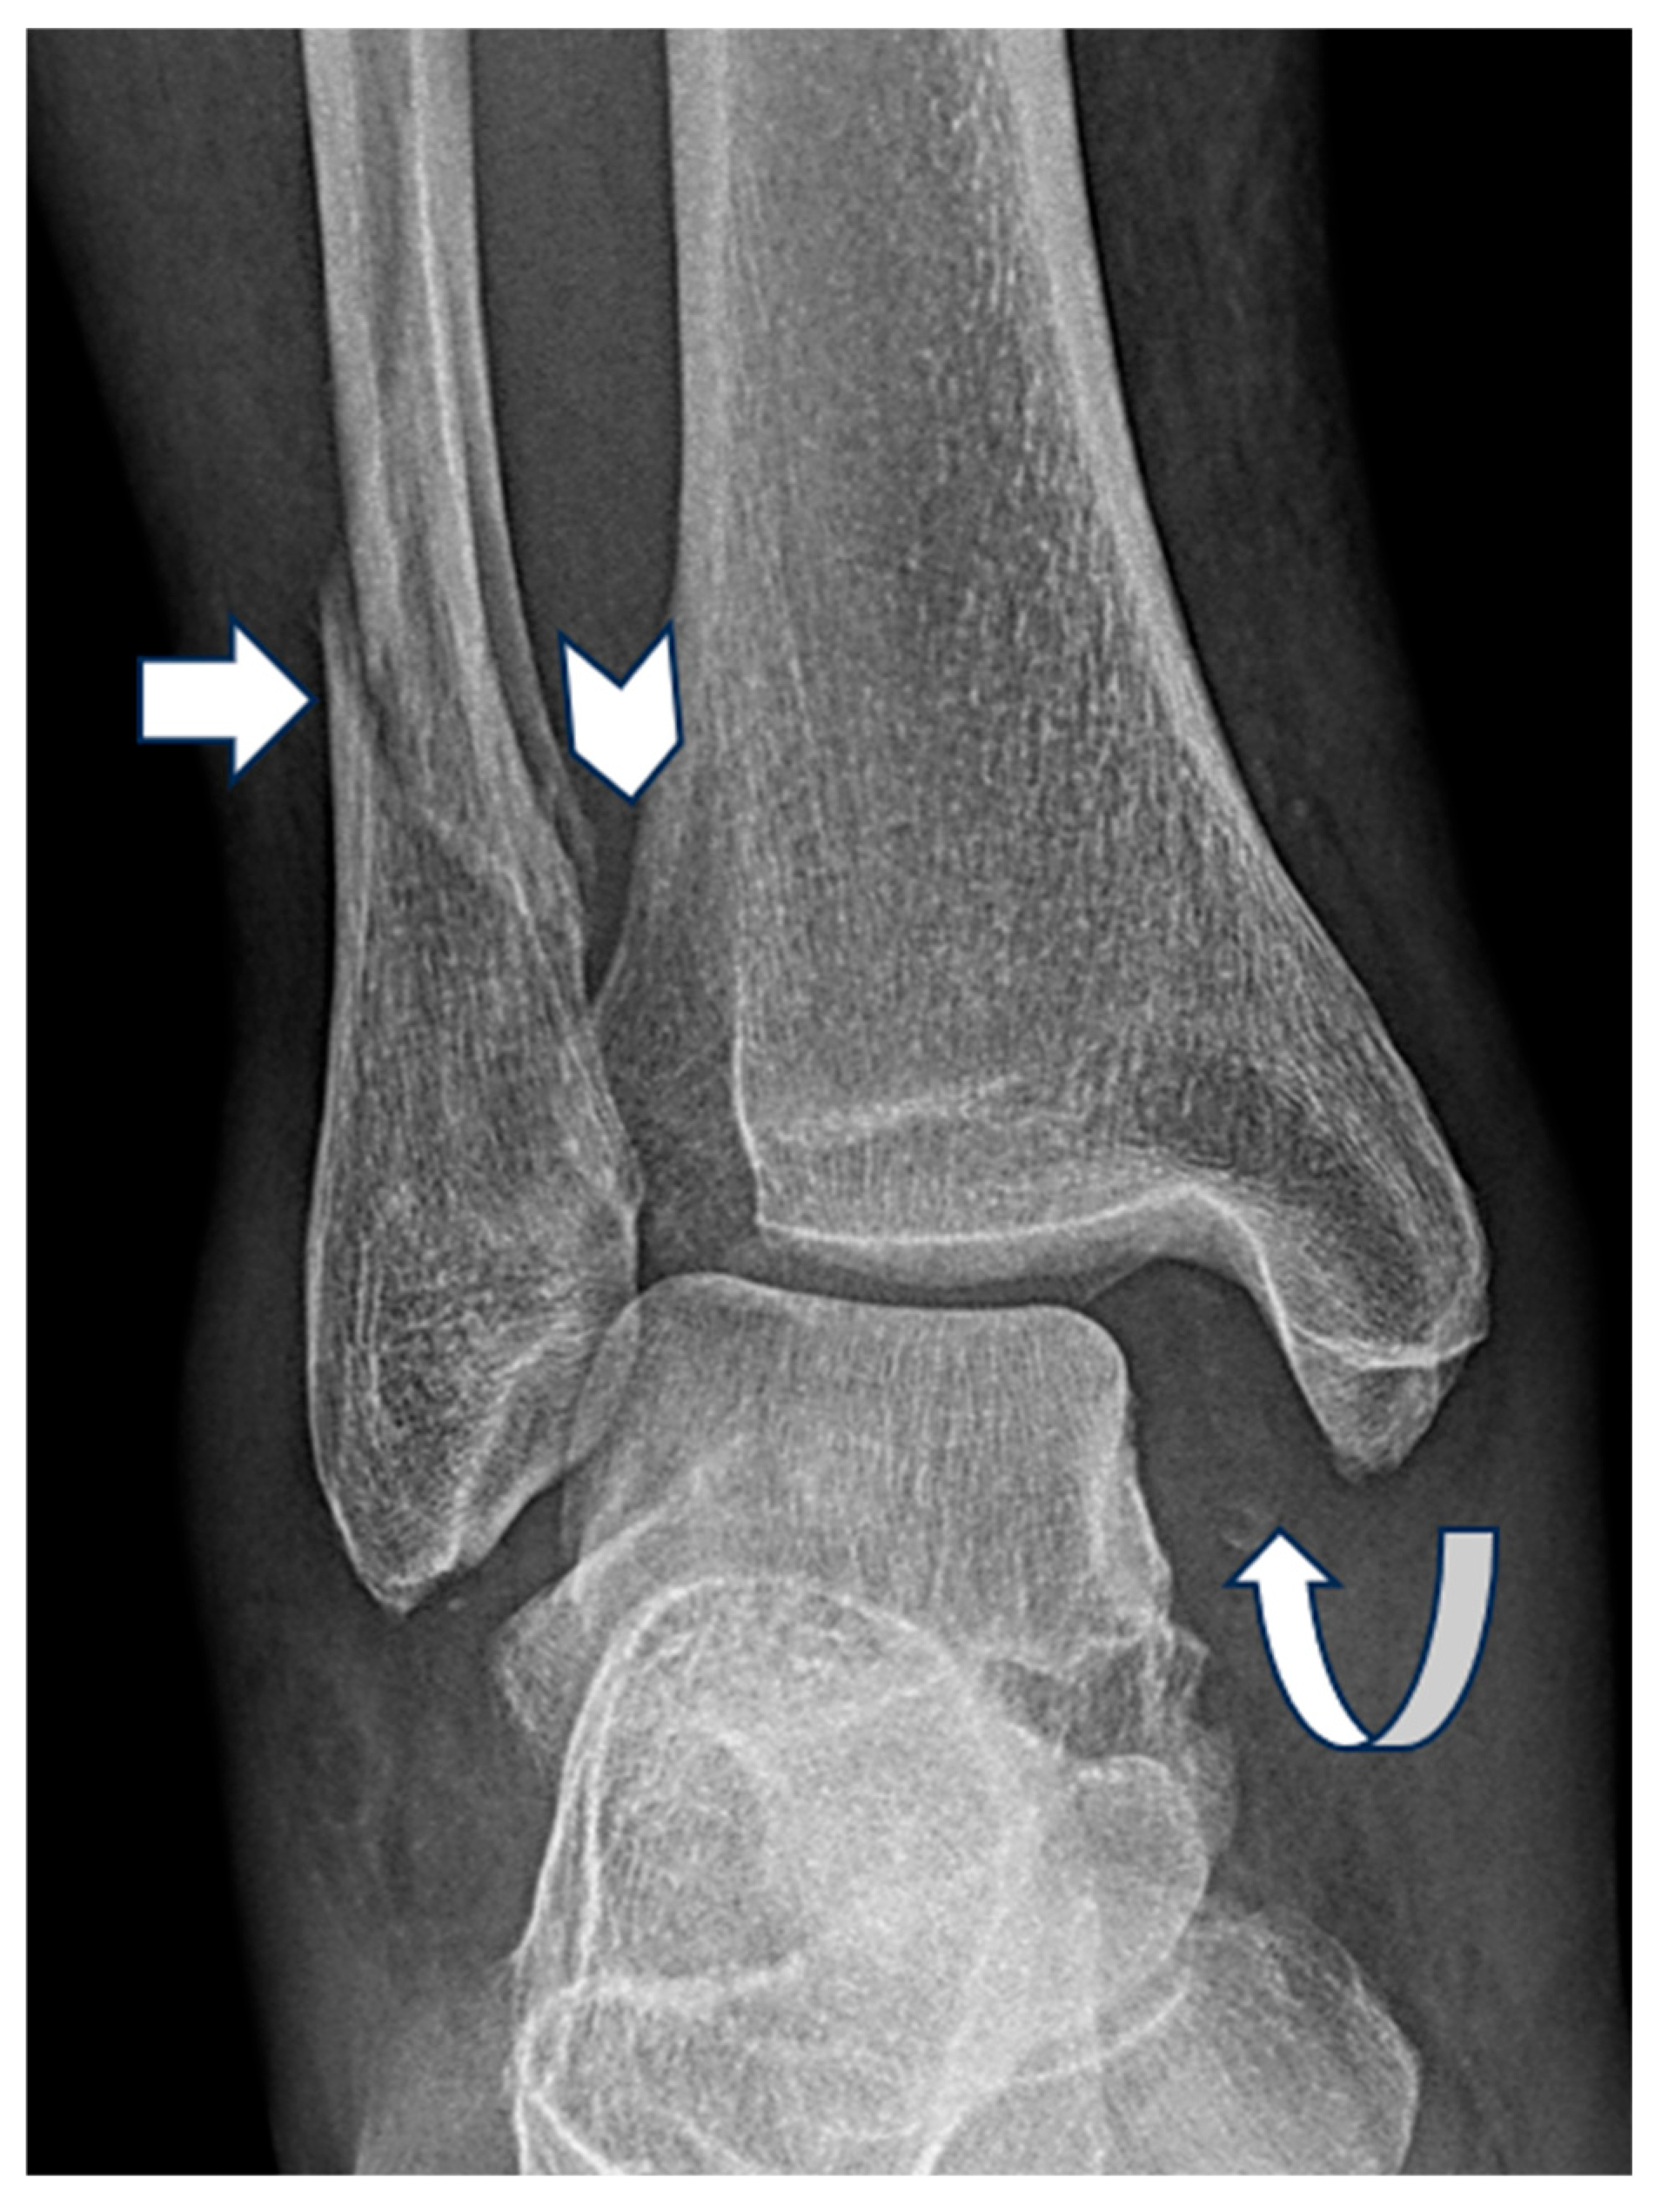

| Pattern (n) | Measurement | Mean ± Standard Deviation (mm) |

|---|---|---|

| Weber A (127) | Medial Clear Space | 3.3 ± 1.1 |

| Lateral Clear Space | 4.2 ± 1.4 | |

| Superior Clear Space | 3.4 ± 0.7 | |

| Weber B (216) | Medial Clear Space | 4.4 ± 2.4 |

| Lateral Clear Space | 4.4. ± 1.5 | |

| Superior Clear Space | 3.6 ± 0.7 | |

| Weber C (130) | Medial Clear Space | 5.7 ± 3.6 |

| Lateral Clear Space | 5.8 ± 2.9 | |

| Superior Clear Space | 3.7 ± 0.9 |

| Pattern (n) | Medial Clear Space | Frequency |

| Weber A (127) | <4 mm | 90 (70.9%) |

| 4–5 mm | 33 (26.0%) | |

| >5 mm | 4 (3.1%) | |

| Weber B (216) | <4 mm | 97 (44.9%) |

| 4–5 mm | 83 (38.4%) | |

| >5 mm | 36 (16.7%) | |

| Weber C (130) | <4 mm | 32 (24.8%) |

| 4–5 mm | 58 (45.0%) | |

| >5 mm | 39 (30.2%) |